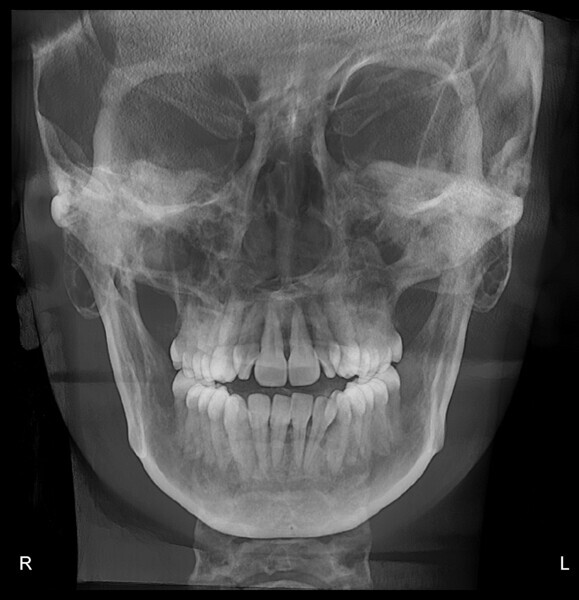

The panoramic radiograph confirmed the presence of all four third molar germs. Notably, there was advanced root resorption in the maxillary arch, although the overall periodontal health appeared good (Fig. 3). The cephalometric analysis showed a Class II skeletal pattern, a vertical growth tendency and posterior mandibular rotation. The maxillary and mandibular incisors were found to be slightly proclined (Fig. 4).